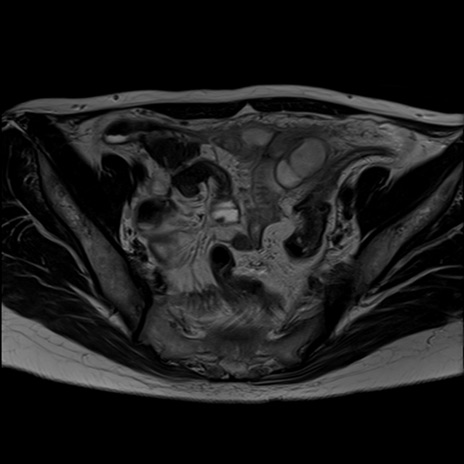

症例39 T2WI(横断像)

MRI(4日後)